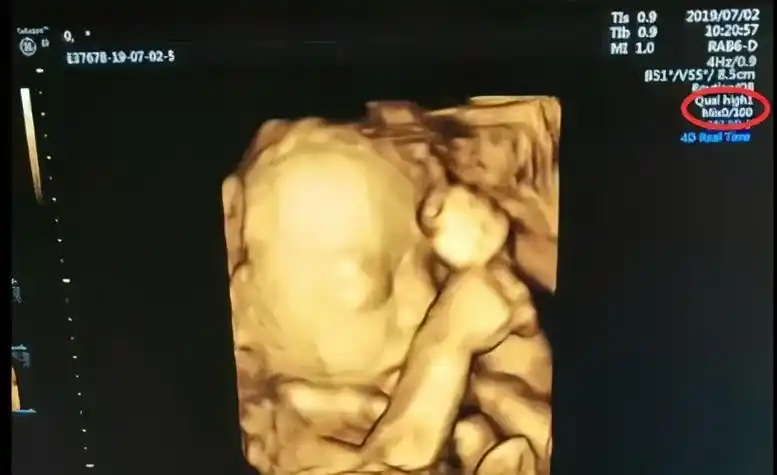

中间那个是小鸡鸡吗?

翻看昨天录的四维视频,被我看到了小鸡鸡